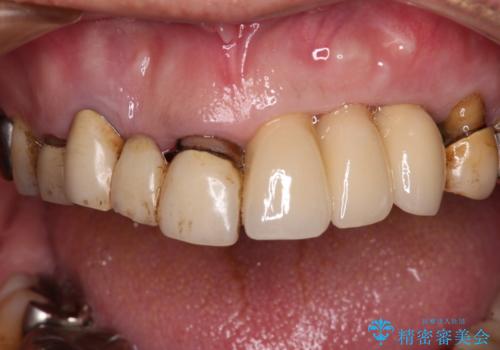

転倒で折れてしまった前歯 インプラントによるオールセラミックブリッジ治療

- 転倒により前歯3本が折れてしまったとのことで、インプラントによる治療を希望して来院された患者様です。

既に近医で真ん中の歯1本は抜歯されており、その隣の2本も破折していると言われたとのことでした。

診断をした結果、前医の診断の通り、2本とも破折しており、既に抜去している歯を含めて3本の抜歯が必要な状態でした。

抜歯する歯の両隣も治療が必要と思える歯であったため、広範囲なオールセラミックブリッジによる治療も提案しましたが、患者様本人の希望もあってインプラント2本による欠損部のみのブリッジ治療を行うこととしました。

治療により前歯は非常に安定しましたが、インプラント部の両隣、特に反対側の前歯はクラウンのやり直しが必要な状態であったので、今後反対側の治療も実施していく予定です。